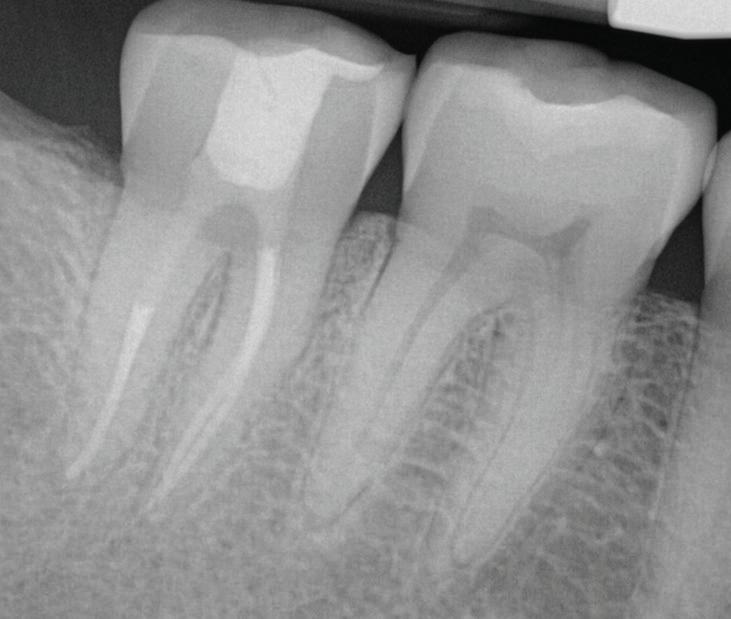

Fig 1. Proximity of root apices to vital structures. A. The periapical radiograph indicates that the apices of the mandibular right second molar and second premolar are in proximity to the inferior alveolar and mental nerves. B. A coronal CBCT image more clearly demonstrates the proximity of the molar apex to the inferior alveolar nerve. C. A coronal CBCT image more clearly demonstrates the proximity of the premolar apex to the mental nerve.

The inferior alveolar canal courses closely beneath the apices of mandibular molars, particularly second molars. Studies have shown that in more than 25% to 30% of patients, the inferior alveolar canal lies within 1 mm of the root apices of second molars; the prevalence is even higher in female and older patients due to reduced bone volume (Fig 1).8

In the endodontic stage, conservative endodontic preparation and obturation with modern techniques are performed as they are for any tooth. All endodontic procedures are performed under an operating microscope to maximize visualization and illumination of the fracture line (Fig 1). The coronal portion of the newly placed gutta percha is removed 2 to 3 mm below the deepest extent of the crack in the affected canal to prepare for intraradicular barrier placement (Fig 2). Gutta percha is also removed 2 to 3 mm into the other noncracked canal orifices in the tooth to prepare for traditional orifice barriers. Microscopic transillumination with a fiber-optic light, in which an LED light probe is placed against buccal or lingual tissues overlying the roots, is utilized to illuminate the root and enhance visualization of the crack (Fig 3). A flowable resin-modified glassionomer or composite resin is then placed in this newly created void from the level of the gutta percha to the floor of the pulp chamber in all canal orifices (Fig 4). A composite resin core is then placed to permanently restore the endodontic access. If a temporary or permanent crown is not placed immediately after the endodontic procedures, the tooth is reduced

Periapical radiograph at the completion of the endodontic protocol. Resin-modified glass ionomer cement is placed as an intraradicular barrier in the distal canal, along the pulpal floor, and as an orifice barrier in the mesial canals.

Fig 2. Gutta percha removed 2 mm apical to the terminus of the fracture (arrows).